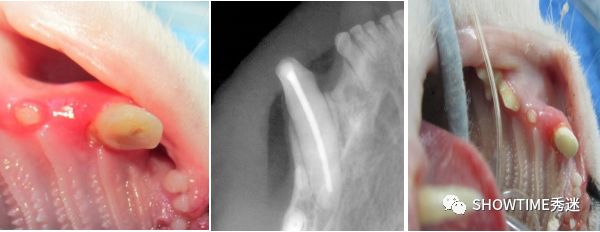

一种是活髓盖髓术,需要在断牙3天内进行,毛孩子不能有牙髓炎或可复性牙髓炎的恒牙、以及牙根尚未发育成熟的年轻恒牙。如果牙齿折断超过 3 天以上,牙髓感染可能深入牙根,这时候用活髓治疗就来不及了,家长要谨慎选择。

犬齿的根管治疗手术前后